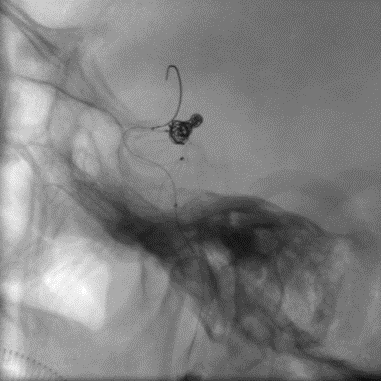

7. 选择好工作角度,开始!对于这类的分叶状(或者有子瘤的“葫芦状”)动脉瘤,我们一般采用分部填塞的方式,以期达到瘤囊内的致密填塞。

工作角度

分步栓塞

载瘤动脉严重狭窄,必须要扩张,然而动脉瘤相对宽颈,载瘤动脉扩张前致密裸栓可能性不大,所以子瘤也要尽量致密栓塞,减少扩张载瘤动脉血流冲击增多后动脉瘤的出血可能性!

而对于第三种,我们完全可以把它视为两个动脉瘤,分别做致密填塞

8. 填到瘤颈,这里有一点小Tips:对于这样的案例,我们可以利用微导管或微导丝的弓形来作为弹簧圈的“支撑”,从而进行瘤颈部的处理,这种方法同时保证本就纤细的载瘤动脉的通畅度,而不增加额外操作。事实上,韩国和欧洲原来也有相似技术的文献报道,效果很好。在这里,我们使用确保远端通路的SL10作为支撑导管,Headway 17作为填塞导管,实现了瘤颈部致密填塞。

微导管保护下填塞瘤颈

注:红色箭头为Coiling: Headway 17 Mc,蓝色箭头为Protecting: SL 10 Mc。

微导管/微导丝保护技术